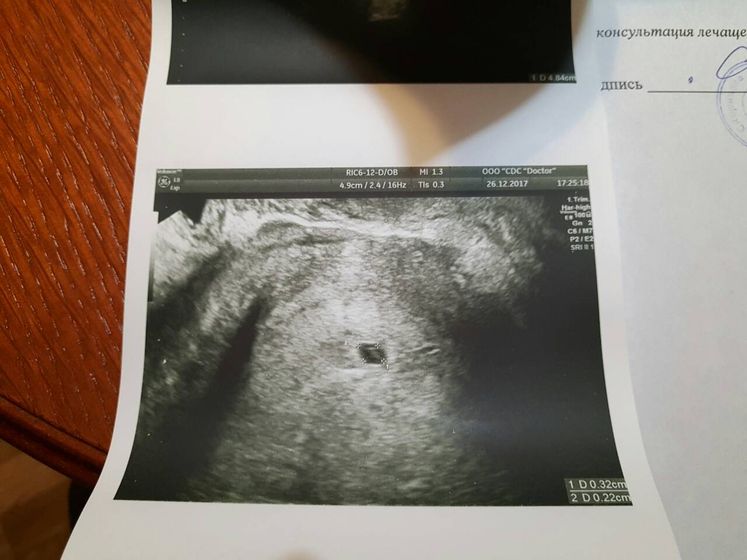

Привет подруженькам) Давно здесь тишина, от моих планюшек ничего не слышно. Хочу поделиться нашей новостью. В начале ноября, по совету своей сестры, я пошла к эндокринологу в Доктор А Фоминой. Она назначила анализы и мне и мужу. Исходя из анализов и тестов увидела у меня инсулинорезистентность, назначила Глюкофаж и витамин Д(последнее и мне и мужу), и еще кучу витаминов, которые я так и не успела купить… Мы начали все это принимать. В Январе сказала снова сдать мне анализы и явиться к ней. Мужу назначила МРТ мозга из-за высокого пролактина, подозрение на аденому… так вот… 24 декабря я затеяла генеральную уборку. Вытирала всюду пыль. И нашла тест. К слову, я давно уже не тестю, так как толку не видела, результат был всегда один, а искать полоски там, где их нет — не по мне. Ну и тут на днях увидела в календаре, что последние месячные у меня были 13 ноября, но и это для меня норма — мои подружки знают, что цикл в 70 дней для меня тоже норма… Ну, раз попался тест под руку, сделаю. И что вы думаете? Секунд через 10 четкая вторая!!! Проморгалась!!! Да, четкая вторая!!! Бегу на кухню к мужу, ору что есть мочи “ты видишь? Ты видишь ее?!” Он говорит “Да! И что это значит?!” Как второклассник) Ревем оба… Бежим в аптеку, покупаю еще два теста и один электронный: “беременна 2-3”. Паника. Выдерживаю три дня. Бегу на УЗИ, боюсь вдруг внематочная, из головы не выходит мой эндометриоз, склерокистоз… Узист расплывается в улыбке “совсем крохотулечка, 3 мм...” Боже… Это существо размером с кунжутное семечко, а я его так люблю… По Узи “маточная беременность 2-3 недели”. Пока все. Ломаем голову, куда вставать на учет. Страх и переживание… Каждый час благодарю Бога и молю.о том чтобы все было хорошо… Знают только муж и мамочка. Вот решилась написать и Вам. Кстати, сразу написала Фоминой, она сказала отменять все, кроме витамина Д. Порекомендовала врача Попову О.Г в докторе А. Если кто что знает, напишите отзыв о ней мне. Люблю Вас всех, спасибо, что выслушали!